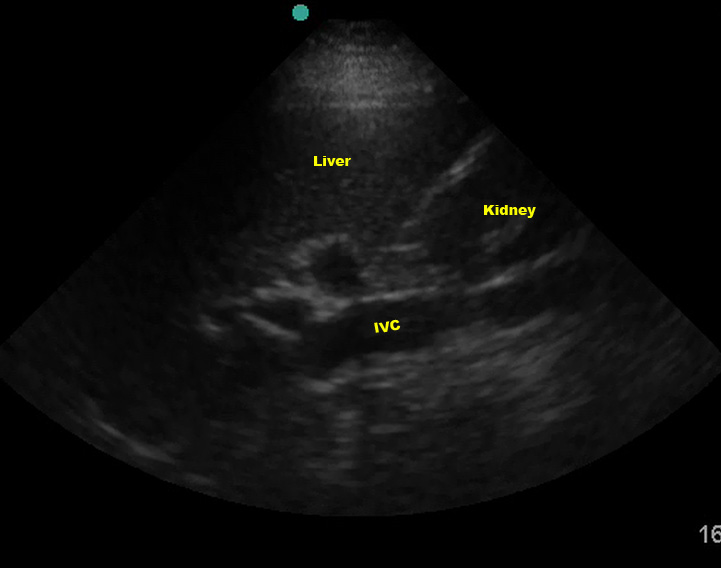

The IVC can also be mistaken for free fluid if you are too posterior.

(Figure 26/26.1)